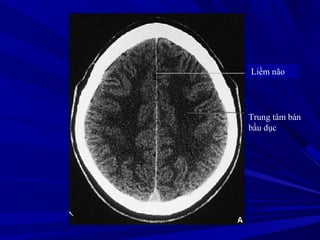

Liềm não

Trung tâm bán

bầu dục